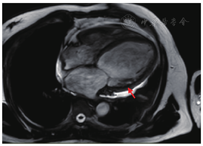

患者男性,57岁,因"胸闷、气短5年,再发加重一周"于2019年4月29日入院。患者5年前(2014年)开始出现胸闷、气短不适,体力活动较前稍有下降,当地医院诊断为"扩张型心肌病",给予对症处理后症状好转,长期口服培哚普利、螺内酯、琥珀酸美托洛尔缓释片。2016年症状再发,当地医院行超声心动图检查:左心室舒张末期内径(left ventricular end-diastolic diameter, LVEDD)63 mm,左心室射血分数(left ventricular ejection fraction, LVEF)44%。冠状动脉造影示:冠状动脉硬化,继续药物治疗,未规律复查。一周前患者感冒后咳嗽、咳痰,胸闷、气短逐渐加重,稍重体力活动即感胸闷,夜间可平卧入睡,偶有阵发性呼吸困难,双下肢无水肿,为进一步诊治就诊我院门诊,门诊以"扩张型心肌病"收治入院。既往发现血压高10年,最高150/120 mmHg(1 mmHg = 0.133 kPa),目前口服培哚普利,血压控制不详。入院体格检查:体温36.5 ℃,脉搏106次/min,呼吸频率21次/min,血压145/97 mmHg。神志清楚,颈软,颈静脉无怒张;双肺呼吸音清,双肺未闻及干湿性啰音;心界不大,心率106次/min,律不齐,可闻及早搏,约15次/min,各瓣膜听诊区未闻及杂音;腹平软,无压痛及反跳痛,肝脾肋下未及;双下肢无水肿,双侧足背动脉搏动对称、良好。辅助检查:血常规:中性粒细胞百分率52.90 %,白细胞计数、红细胞计数、血红蛋白水平、血小板计数均正常;凝血功能:凝血酶原时间17.4 s,活化部分凝血活酶时间(activated partial prothrombin time, APTT)25.9 s,凝血酶原时间国际标准化比值(international normalized ratio, INR)1.15;血生化:血钾4.42 mmol/L,血清肌酐99 μmol/L,肾小球滤过率73 mL/min,血清尿酸631 μmol/L;N末端B型利钠肽前体(N terminal pro-B type natriuretic peptide, NT-pro BNP)2430.00 pg/mL;心肌酶谱:心肌肌钙蛋白T 18 ng/L(参考范围0~14 ng/L);血浆D-二聚体0.34 mg/L。心电图:窦性心动过速,心率103次/min,QRS 142 ms,室内传导延迟,室性期前收缩(室早)。超声心动图:左心房前后径55 mm,右心房前后径52 mm,LVEDD 68 mm,LVEF 36%,左心扩大,右房扩大,室间隔、左室壁运动幅度普遍减低,二、三尖瓣轻-中度返流,肺动脉高压(轻度),左心收缩功能减低,心包少量积液。胸片:肺淤血,肺无实变,右膈光整,左侧胸腔少量积液。主动脉结宽,肺动脉段平,左心房、室增大。心胸比率:0.56。综上诊断:1.扩张型心肌病,心功能Ⅲ级(NYHA心功能分级);2.心律失常,室性期前收缩;3.高血压病3级(极高危)。患者入院后给予沙库巴曲缬沙坦、美托洛尔、呋塞米及螺内酯口服。患者入院后频繁发作室性期前收缩(室早),并发作室性心动过速(室速),给予静脉泵入尼非卡兰可转复为窦性心律,同时加用口服胺碘酮治疗室性心律失常,静脉24 h持续泵入左西孟旦改善心功能。入院第9天(2019年5月8日)行心脏磁共振成像检查(图1)示:LVEDD 71 mm,左心室收缩末期内径(left ventricular end-systolic diameter, LVESD)66 mm,LVEF 15%,右心室射血分数(right ventricular ejection fraction, RVEF)27%,左心室扩大,左心室收缩功能明显减低,右心室收缩功能减低,左心室血栓形成,大小分别为2.2 cm×1.2 cm及2.2 cm×0.7 cm,心肌灌注显像显示心肌未见明显缺血,心肌延迟显像显示室间隔及左室下壁基底段至中间段心肌中层纤维化形成。当日复查超声心动图示:LVEDD 71 mm,LVEF 28%,1、左心扩大,右心房扩大;2、左心室血栓形成(室间隔处可见稍高回声团附着,范围约5.3 cm×1.2 cm);3、室间隔、左室壁运动幅度普遍明显减低;4、二、三尖瓣轻度反流;5、肺动脉高压(轻度);6、左心收缩功能减低;7、心包少量积液。立即给予肝素抗凝治疗,APTT维持40~60s。患者入院后经规范药物治疗,心功能仍为Ⅲ~Ⅳ级,且存在频发室早,短阵室速,抗心律失常药物治疗效果不佳,猝死风险高,遂于入院后第10天(2019年5月9日)行心脏再同步治疗-除颤起搏器(cardiac resynchronization therapy-defibrillator, CRT-D)植入术,术后继续肝素抗凝治疗,术后第3天(2019年5月11日)患者突发失语,右侧肢体偏瘫,肌力0级,考虑急性脑血管意外,急诊行头颈部CTA检查(图2)示:左侧大脑中动脉起始部及以远闭塞,左侧大脑前动脉A2段以远闭塞可能。复查超声心动图提示未见心室血栓,考虑心室血栓脱落所致,神经内科急会诊后建议急诊取栓手术,于发病后约2小时行急诊取栓术,术后患者神志清楚、四肢肌力恢复正常,但仍失语。患者脑梗塞急性期,出血风险高,多次复查心脏彩超未见心室血栓,神经内科会诊建议低剂量抗凝预防血栓形成,术后给予利伐沙班片15 mg,1次/d,口服抗凝治疗,行血浆抗Xa活性测定为0.27IU/L,考虑抗凝有效。取栓术后第2天(2019年5月12日)复查头颈部CTA(图3)提示原左侧大脑中动脉起始部及左侧大脑前动脉A2段以远均显影良好,原闭塞已通畅。患者于2019年5月23日康复出院。随访6个月(见表1),患者LVEDD显著缩小,LVEF及NT-pro BNP水平恢复正常,遗留吐词不清。